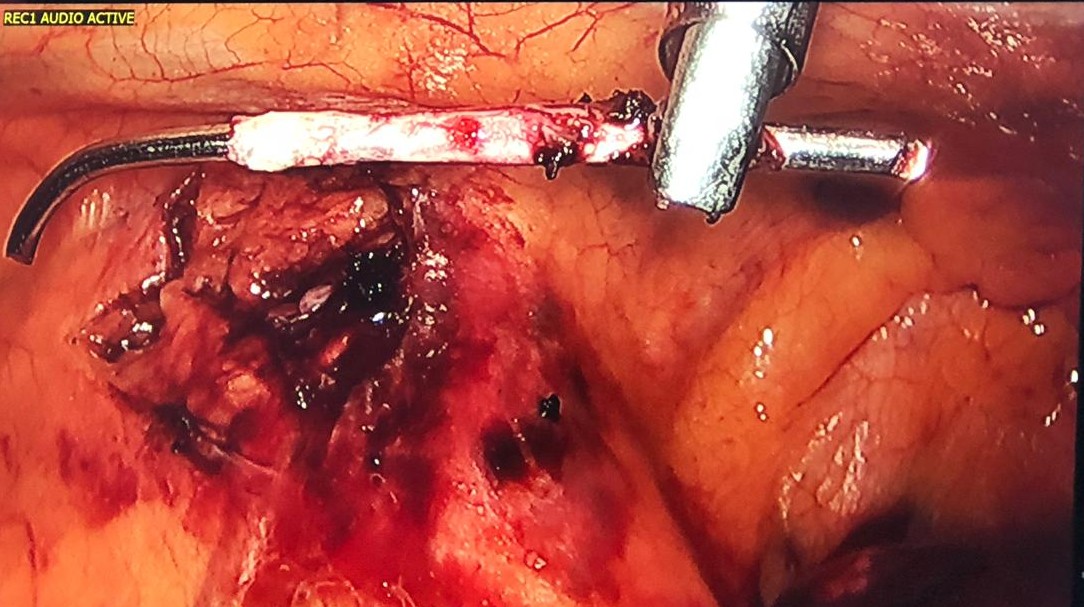

Figure 7. With the aid of an energy device, the authors dissected the tissues around the foreign body, in front of the phrenic nerve like in a thymectomy, and the K-wire was easily removed. It was not hooked to the left brachiocephalic vein.

Figure 8. Extracted K-wire with its distal end bent over to avoid migration measuring approximately 5 cm.